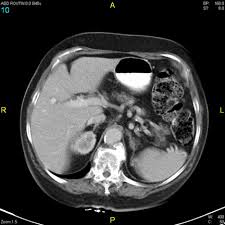

Then I'll head to the CT suite where I'll swallow the peach-flavoured radiactive juice and get hooked up to the I.V. that will provide contrast, both of which are designed to light up my insides during the computed tomography (CT) scan. This test will create photos of my abdomen, like the one seen below, that a radiologist will interpret.

I'll discuss these test results with my doctor tomorrow afternoon. That's when we'll know if the chemo and Olaparib did their job to shrink the tumour and kill those cancer cells. While I'll give blood tomorrow, I won't know my CA-125 right away. Before my last chemo, it was 77 (under 35 is normal). I was disappointed with that number, but my nurse seemed happy because it keeps getting smaller. I guess because I didn't have surgery to remove the tumour, it isn't dropping as quickly as I expect or want.